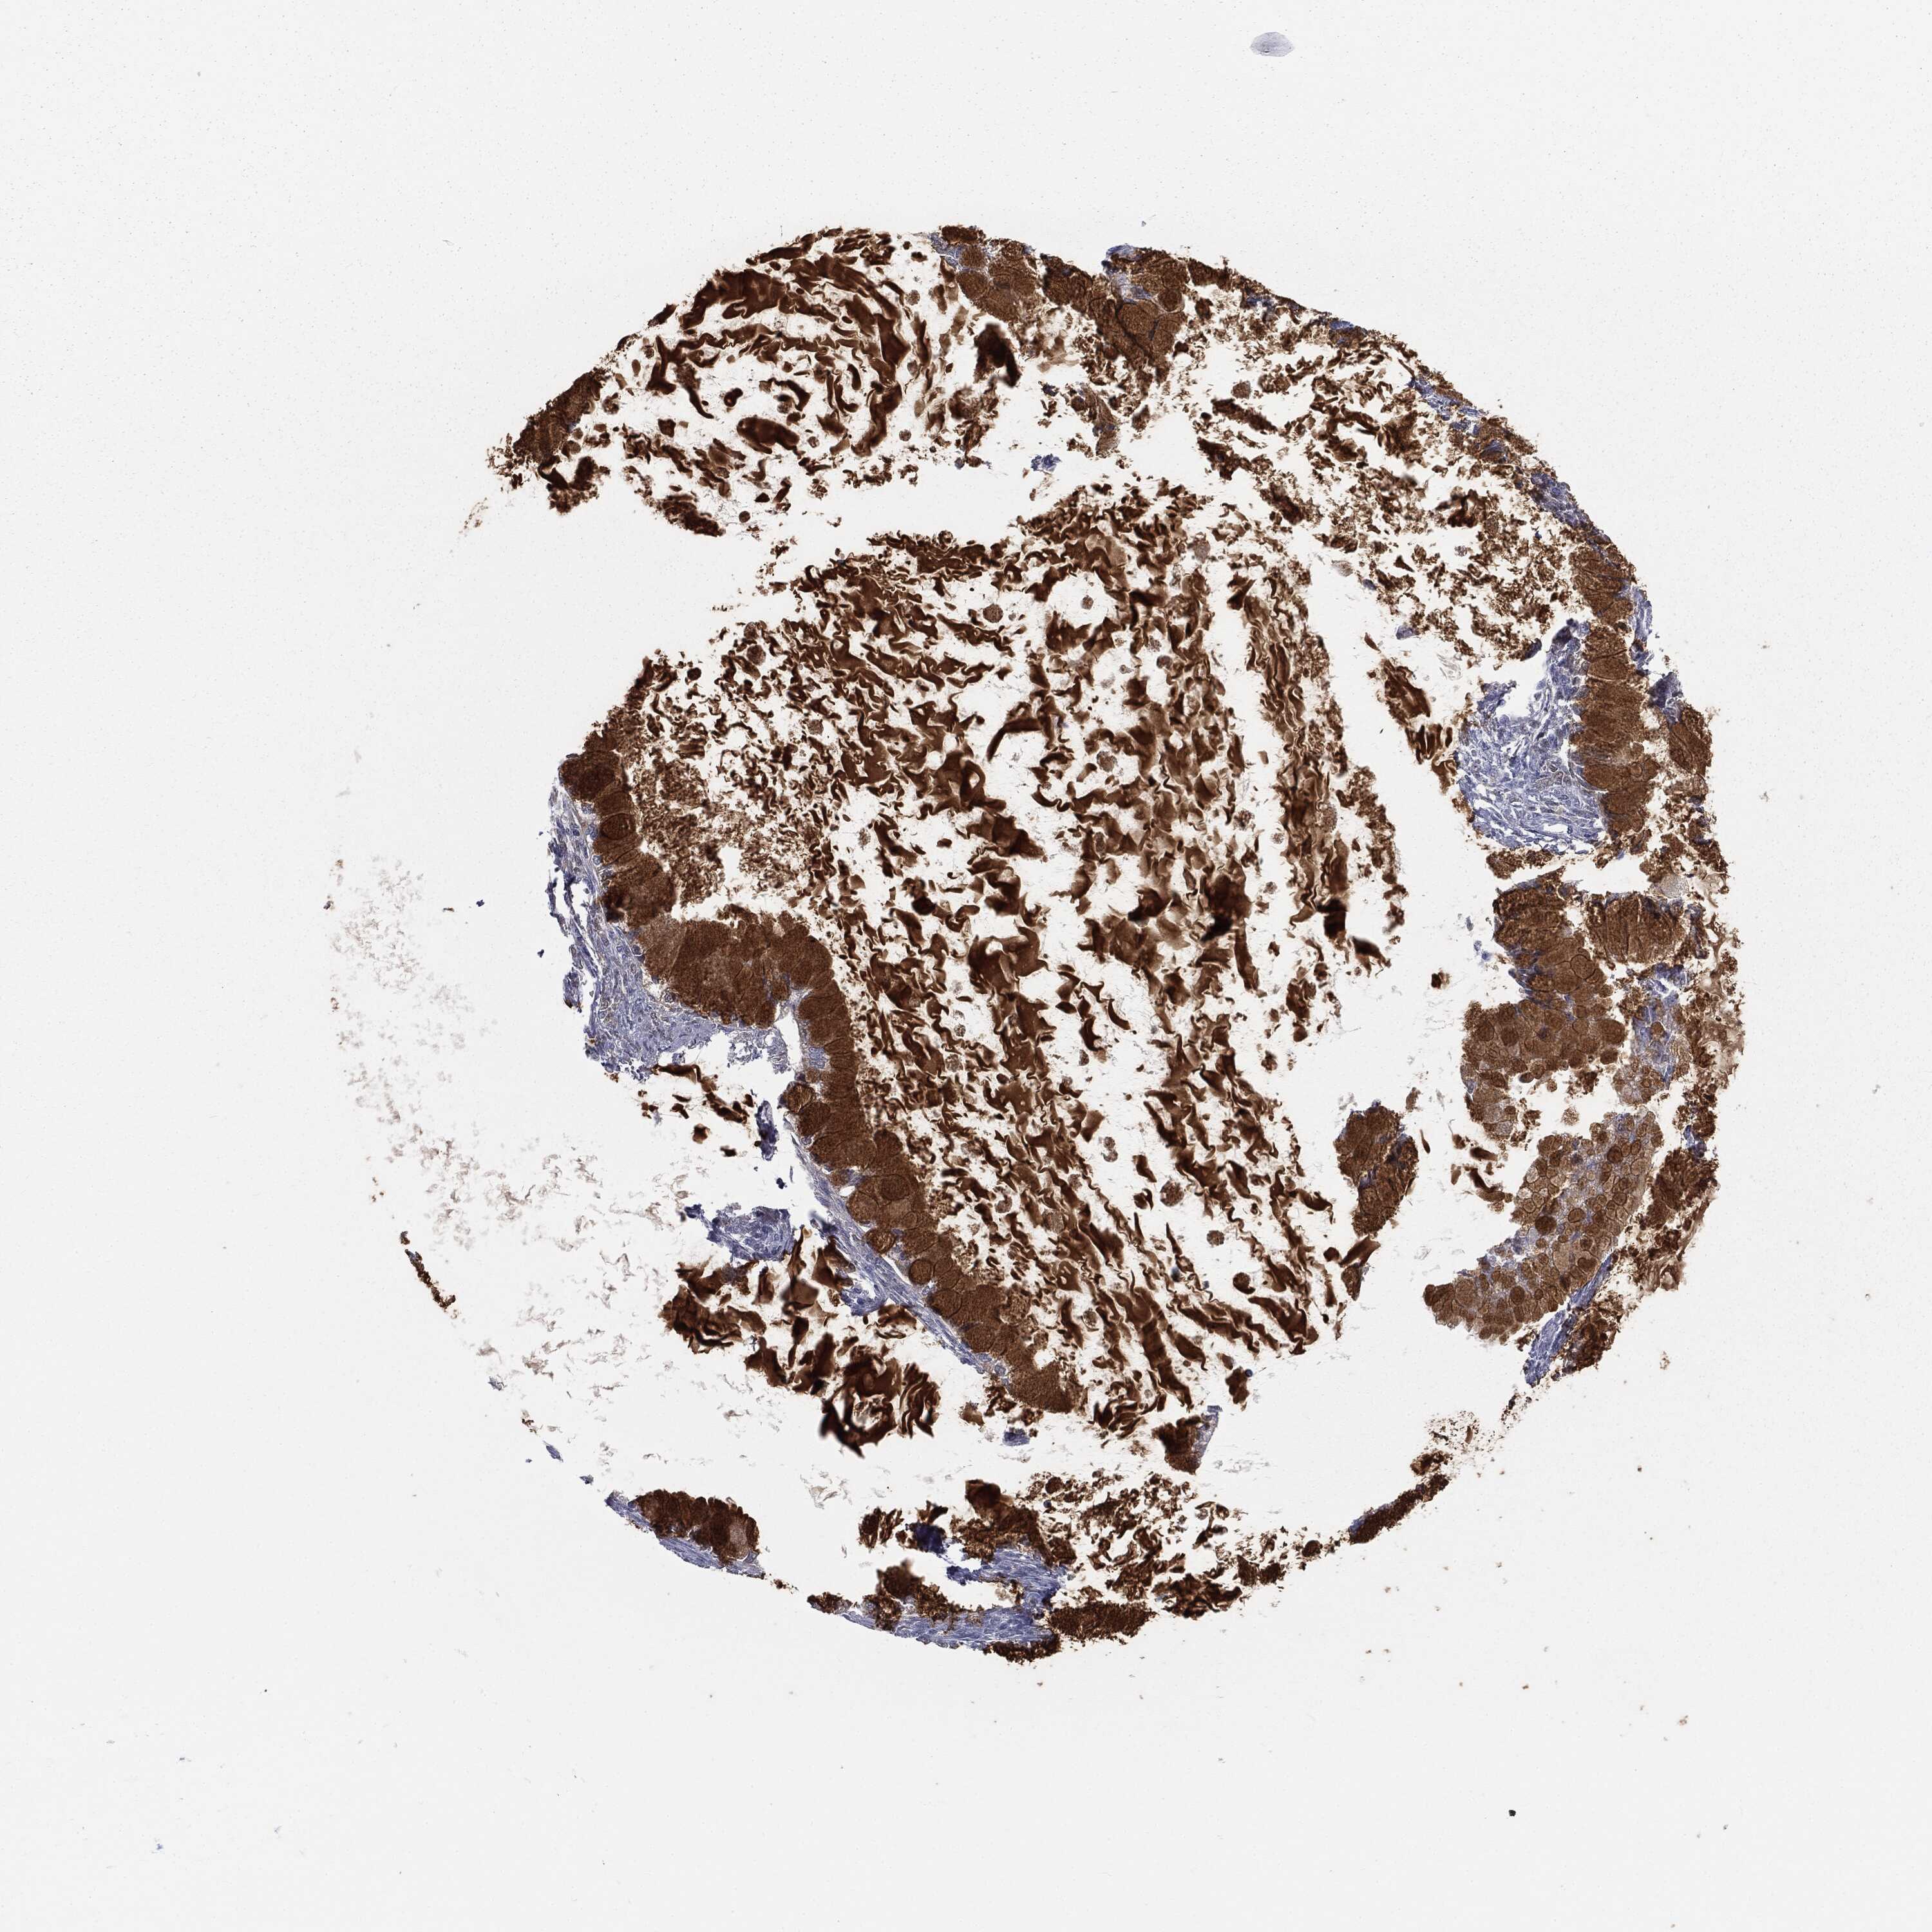

OVARIAN CANCER - Protein expressioni

A mouse-over function shows sample information and annotation data. Click on an image to view it in a full screen mode. Samples can be filtered based on level of antibody staining by selecting one or several of the following categories: high, medium, low and not detected. The assay and annotation is described here.

Note that samples used for immunohistochemistry by the Human Protein Atlas do not correspond to samples in the TCGA dataset.

Antibody stainingi

Antibody staining in the annotated cell types in the current human tissue is reported as not detected, low, medium, or high, based on conventional immunohistochemistry profiling in selected tissues. This score is based on the combination of the staining intensity and fraction of stained cells.

Each image is clickable and will lead to virtual microscopy that enables deeper exploration of all samples and also displays staining intensity scores, fraction scores and subcellular localization as well as patient and tissue information for each sample.

HPA040615

HPA070378

HPA077637

CAB002774

CAB009395

Cystadenocarcinoma, serous, NOS